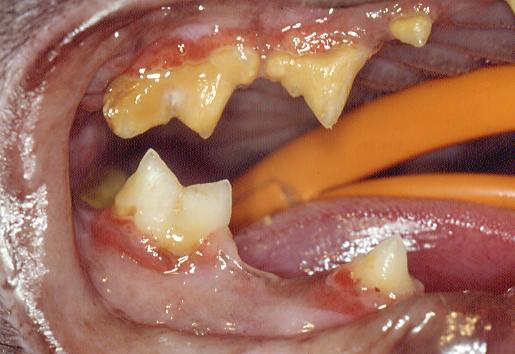

Advanced feline periodontal disease case which may include FORL's

The extraction techniques for cat teeth in the main follow those of dog teeth. Exceptions exist where subgingival resorptive lesions (FORL's or "neck lesions") damage teeth roots. Teeth affected by FORL's rarely have a morphologically intact root for extraction. In these circumstances, amputation of the crown and the root tissue, immediately below the alveolar bone crest, may be permissible.